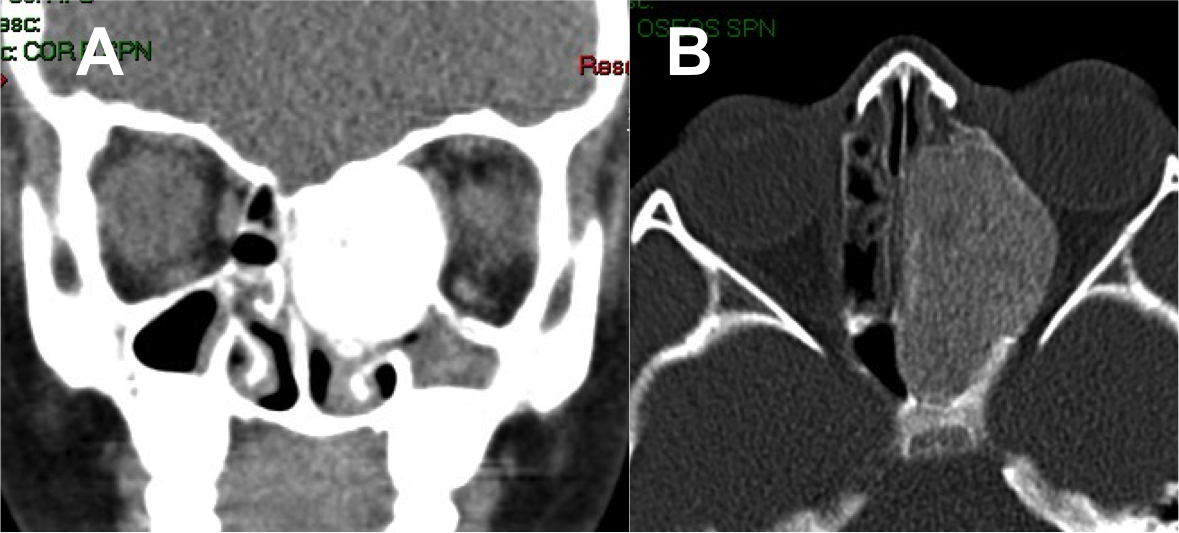

Introducción: La cirugía endoscópica endonasal se ha convertido en una herramienta fundamental para el manejo de patologías que comprometen la base de cráneo. En casos bien seleccionados, estas técnicas permiten resecciones quirúrgicas con una menor morbilidad sin comprometer los principios oncológicos de resección. Con el desarrollo de instrumental especializado, nuevas tecnologías y la experiencia de los cirujanos, la cirugía endoscópica endonasal se usa cada vez más en cirugía de base de cráneo en niños.

Resultados: Fueron intervenidos 8 pacientes entre los 2 y 14 años, con una edad promedio de nueve años y un seguimiento promedio de 16 meses. En el 75% se hizo una resección total del tumor. Un paciente requirió una reintervención y un paciente fue sometido a radiocirugía post-operatoria. 1 paciente falleció a pesar de múltiples intervenciones, quimioterapia y radioterapia.

Conclusión: La cirugía endoscópica endonasal para tumores de base de cráneo puede ser utilizada de forma segura en los pacientes pediátricos, es una técnica que en casos bien seleccionados pueden ofrecer excelentes resultados disminuyendo la morbilidad y complicaciones de las técnicas abiertas.